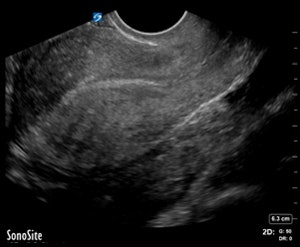

ER-performed ultrasound (top) was interpreted as not having an intrauterine pregnancy. On radiology ultrasound study (above), a radiologist diagnosed an ectopic pregnancy in the left adnexa. All images courtesy of Dr. Myrna Wallace-Severa.The discrepancy differences could be due to a number of factors, including training and experience, according to the researchers. For example, guidelines from the American College of Emergency Physicians (ACEP) for training pathways and the use of bedside ultrasound recommend that residents perform a minimum of 150 bedside ultrasound scans in their residency training to reach competency.